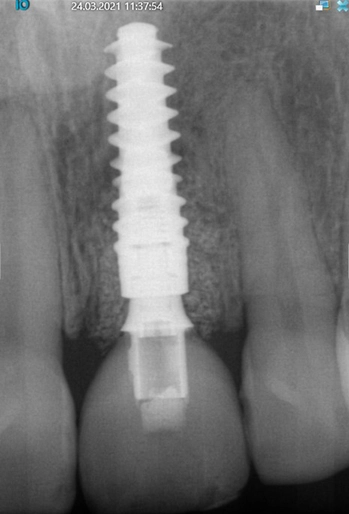

Die Einheilphase verlief komplikationslos. Für die Herstellung der definitiven Implantatkrone wurde eine konventionelle Implantatabformung vorgenommen, um die präzise Passung des Abformpfostens auf dem Implantat am Röntgenbild vornehmen zu können (Abb. 26 und 27).

Theoretisch wäre die digitale Datenerfassung mit dem Intraoralscanner möglich, allerdings sind die Scanpfosten nicht radioopak, so dass eine exakte radiologische Kontrolle nicht möglich ist. Im Dentallabor wurde zunächst das vollkeramische Abutment gefertigt und nach dessen Einprobe die vollkeramische Krone hergestellt (Abb. 28 bis 30). Nach dem Verschrauben der Krone im Mund konnte der Schraubenkanal mit Komposit verschlossen werden. Es zeigt sich eine stabile Situation mit einem gesunden peri implantären Weichgewebe und harmonischem Gingivaverlauf (Abb. 31a und b).